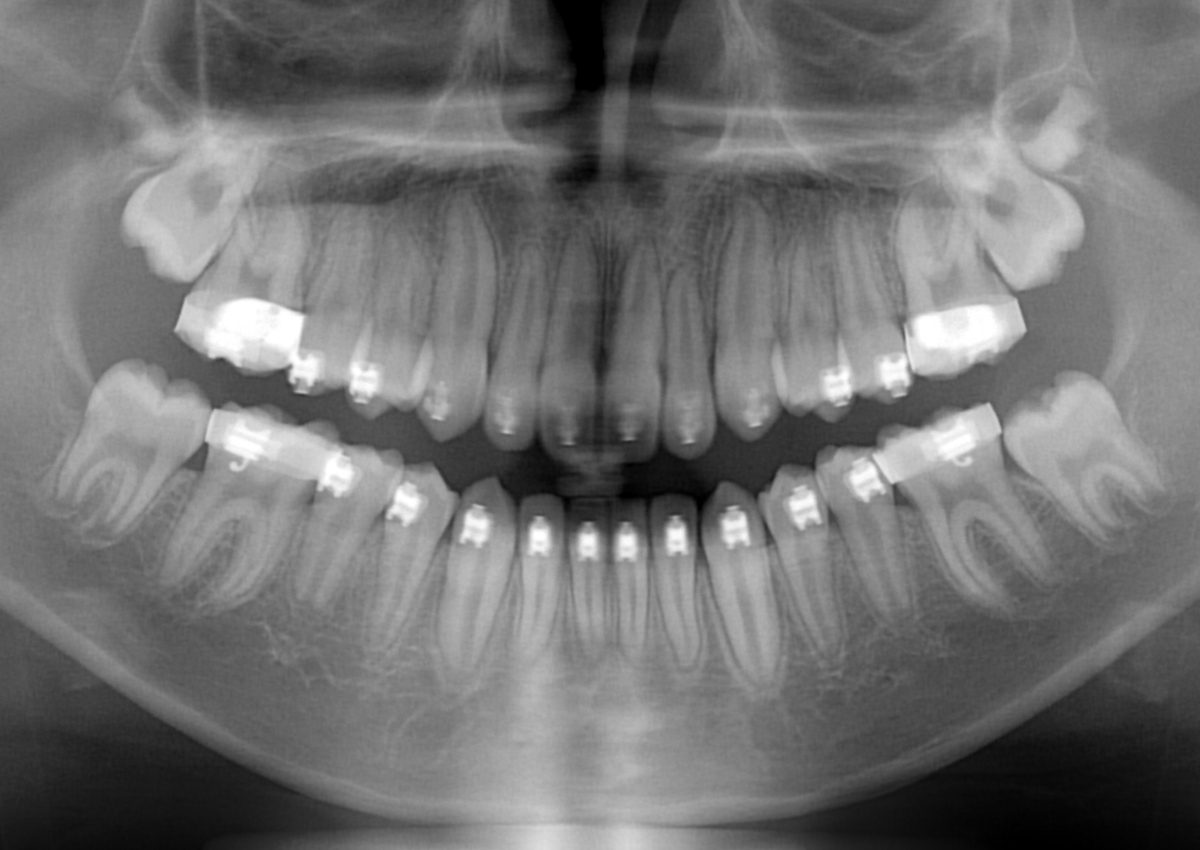

埋伏の治療例(1期)

初診

治療後

年齢

11歳

主訴

左上の糸切り歯が生えてこない

診断

左上3番の埋伏

治療装置

マルチブラケット装置

抜歯部位

非抜歯

治療期間

12か月

リスク

・歯の移動に伴う痛み

・歯根吸収

・歯肉炎、虫歯

費用

¥506,000